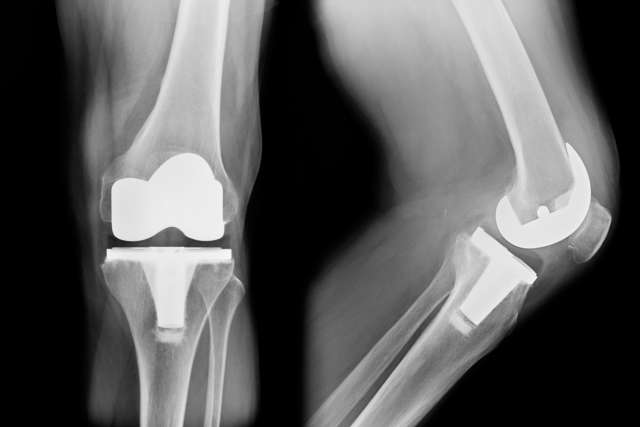

A partial or total joint replacement (arthroplasty) involves removing the damaged portion of the joint or the entire joint and replacing it with artificial parts. Our orthopedic surgeons perform all types of joint replacements, including:

- Knee replacement

- Total joint replacement: We replace the entire joint with a prosthetic device. This is one of the most common procedures we perform. It’s highly effective at relieving pain and restoring mobility when the entire joint is damaged.